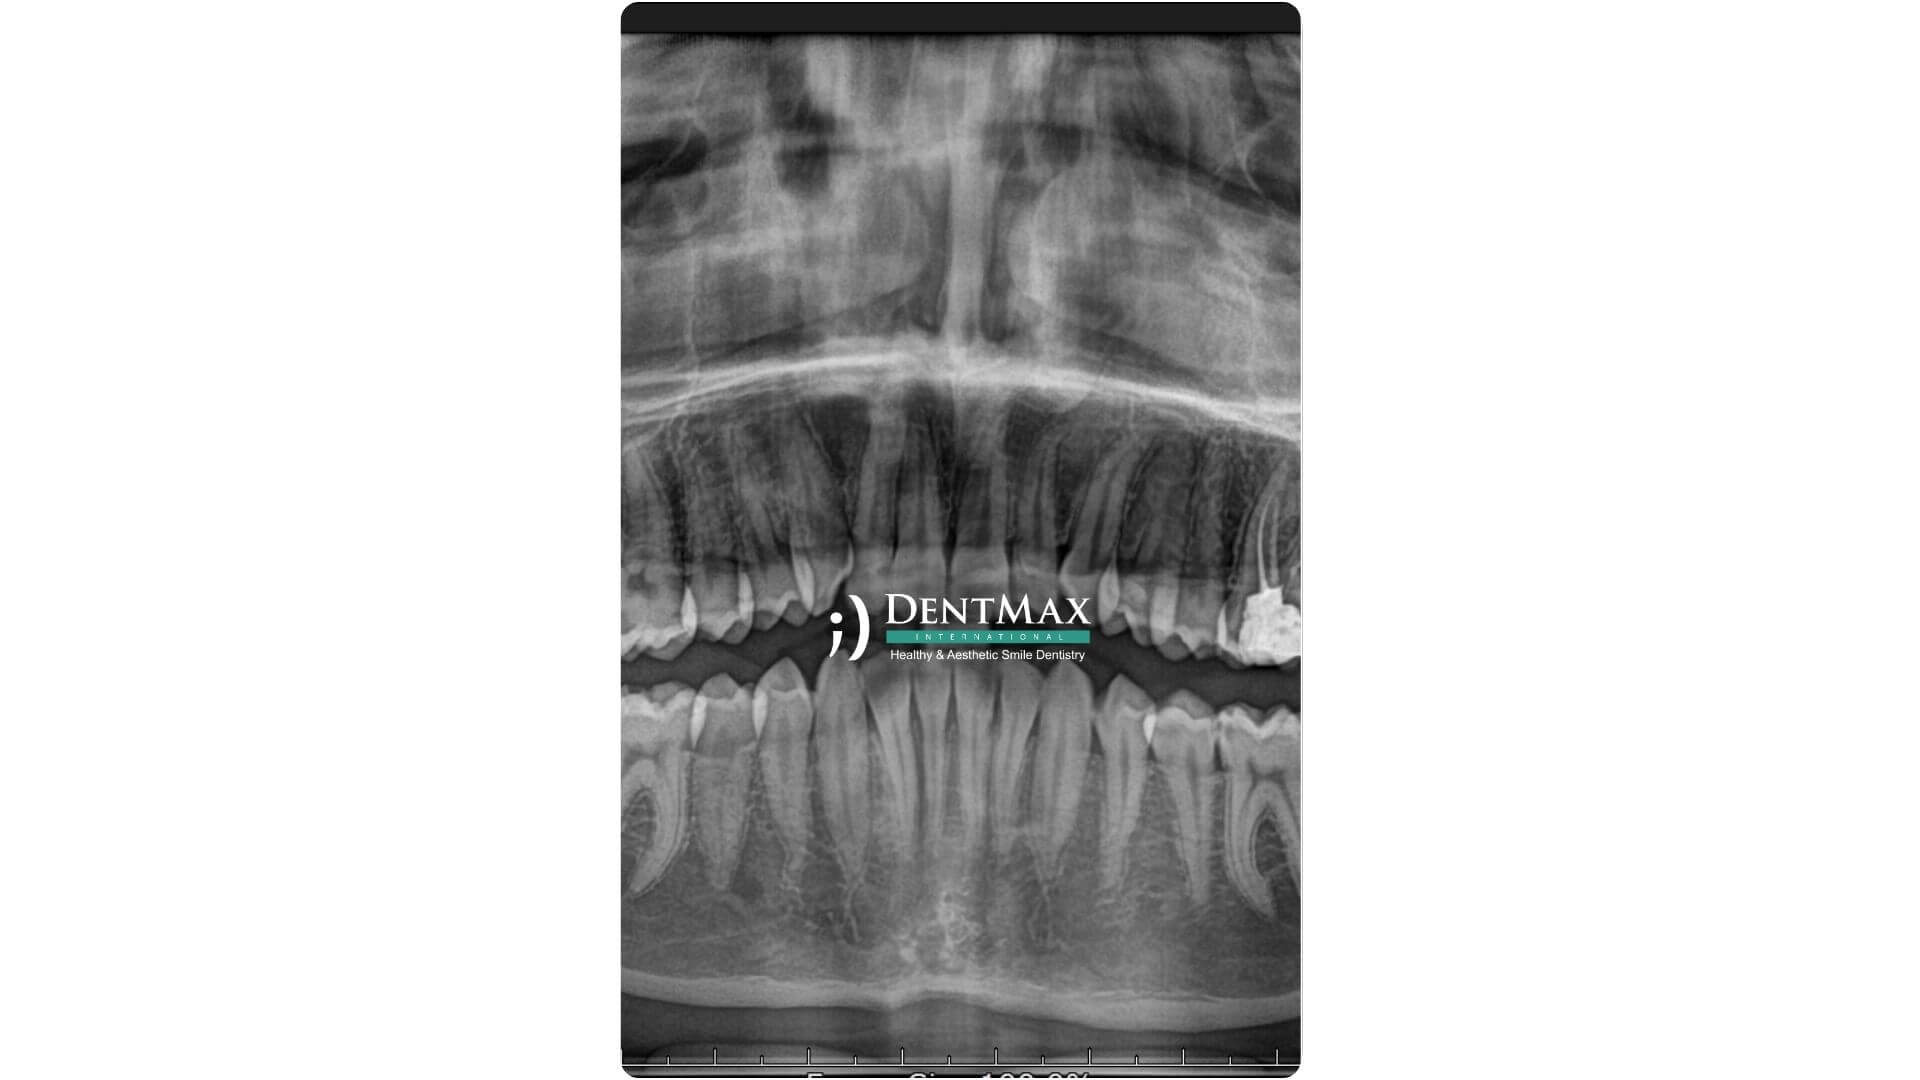

Panoramik röntgen, ağız içindeki tüm dişleri, çene kemiğini, sinüsleri ve temporomandibular eklemleri tek bir filmde gösteren dijital görüntüleme yöntemidir. DentMax’te tanı ve tedavi planlamasında temel rol oynayan bu teknoloji, düşük dozda radyasyonla geniş kapsamlı bilgi sağlar ve teşhis sürecini hızlandırır.

Ağız ve çene bölgesindeki tüm yapıları tek seferde dijital olarak görüntüleyen, hızlı ve ağrısız bir radyolojik tanı yöntemidir.

Hasta cihazın içine başını yerleştirir, hareket etmeden birkaç saniye bekler. Görüntü dijital ortamda anında elde edilir.

İmplant planlaması, gömülü diş değerlendirmesi, çene kırıkları, kist ve tümör taramaları gibi pek çok vakada kullanılır.

Çünkü DentMax’te son teknoloji dijital röntgen cihazlarıyla yüksek çözünürlükte ve düşük radyasyonlu görüntüleme yapılır.

İşlem genellikle 10–15 saniye içinde tamamlanır. Anında görüntü elde edilir ve uzman hekime aktarılır.